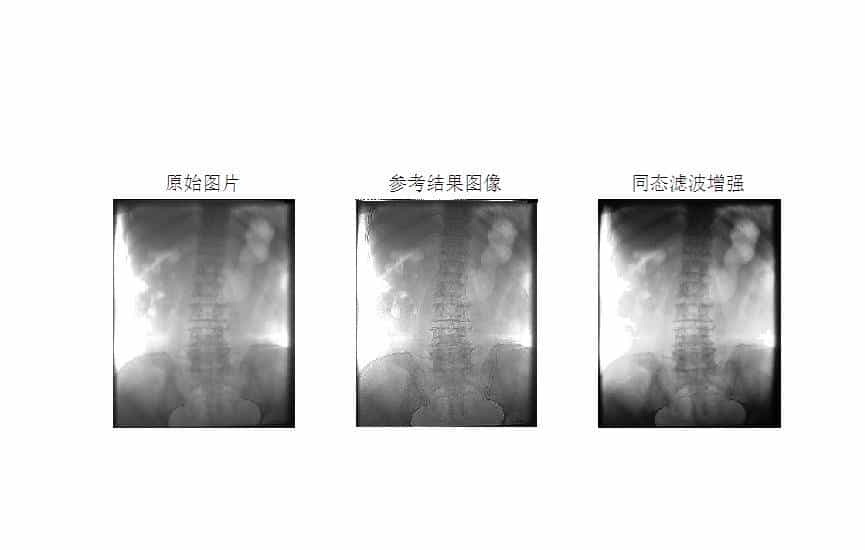

MATLAB环境下使用同态滤波方法进行医学图像增强

同态滤波是一种结合了频率过滤和灰度变换的方法,它以图像的照度反射模型作为频域的处理基础,分别对低频信息进行增强,高频信息进行抑制,可以有效解决图像上照度不均匀和 动态范围过大对图像产生影响的问题,在不损失亮区细节信息的同时,有效增强暗区的细节信息。

本文以医学图像为例,使用同态滤波方法进行医学图像增强。

结果如下: